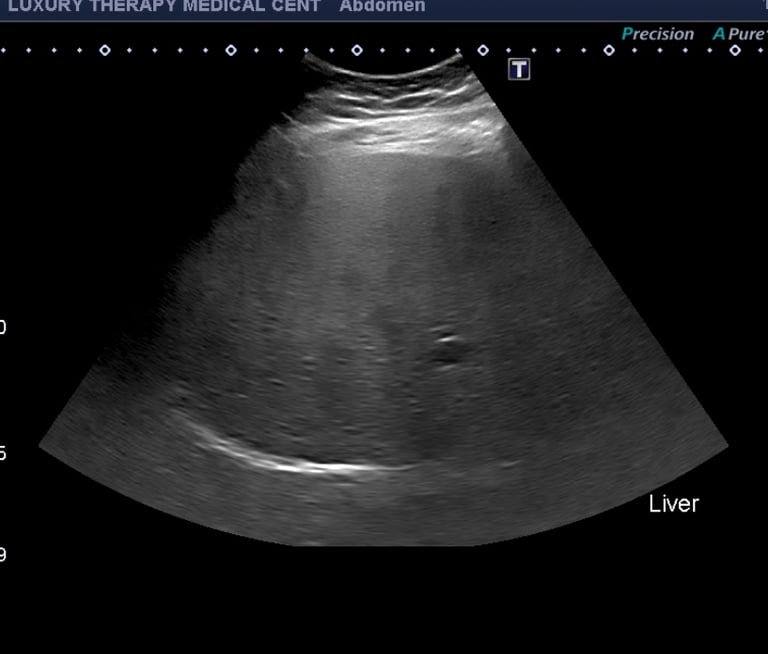

Cómo se detecta el hígado graso

El ultrasonido abdominal es una de las pruebas más comunes y efectivas para detectar el hígado graso. Este examen es:

En el ultrasonido, un hígado graso suele aparecer más brillante o hiperecoico en comparación con el tejido hepático normal.